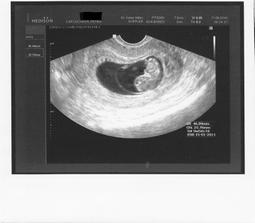

Jak rosteme s Aničkou v bříšku ;o)